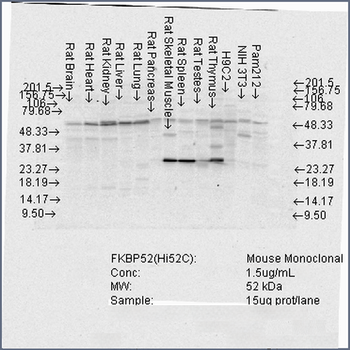

50 μl, 100 μl, 200 μlFKBP52 Antibody: APC [orb147210]

ICC, IF, IHC

Canine, Hamster, Human, Mouse, Rat

Mouse

Monoclonal

APC

100 μgFKBP52 Antibody: Biotin [orb147211]

ELISA, ICC, IF, IHC, WB

Canine, Hamster, Human, Mouse, Rat

Mouse

Monoclonal

Biotin

100 μg